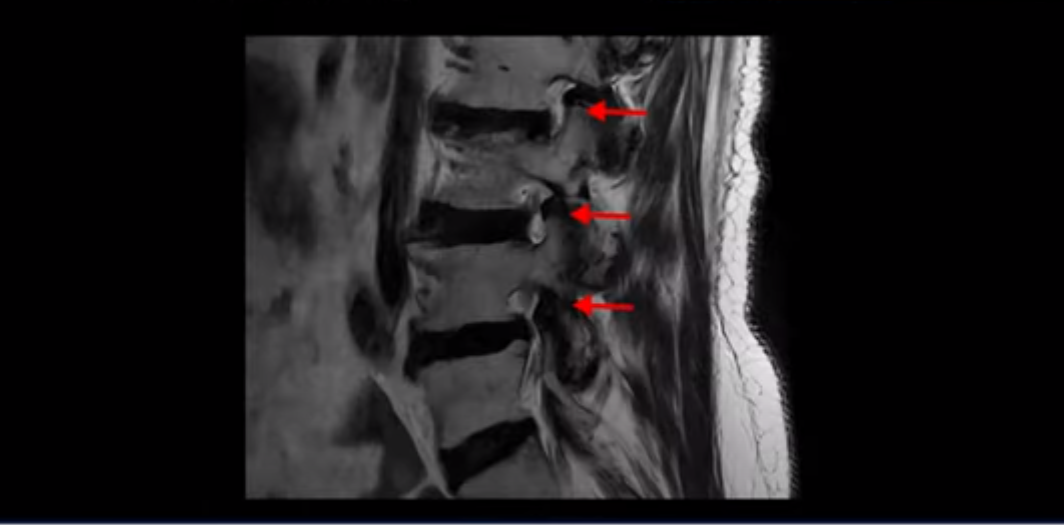

이 환자분은 고관절 쪽이 10년이 넘게 아팠고, 5년 전에는 갑자기 허벅지와 다리가 아파 못 걷게 돼서 허리 수술을 받습니다. 그리고 3년 후에 다시 재발합니다. 고관절 통증은 허리 수술 이후에도 좋아지지 않고 계속 아팠습니다. 수술하고 재발한 이후로 원래부터 아프던 고관절은 물론, 양쪽 엉덩이와 사타구니 및 허벅지가 다 아파서 잘 걷지도 못하고 또 앉거나 누워도 아파서 뒤척거리기도 힘듭니다. 이분 MRI를 보면 여러 마디가 다 안 좋습니다.

4번 5번에는 왼쪽으로 이전에 수술한 자국이 보이는데

수술한 부위에 상처 조직이 생겨 유착된 부위가 보입니다. 왼쪽, 오른쪽 신경 가지가 빠져나가는 추간공을 보면 오른쪽도 여러 마디가 좁아져 있고

왼쪽도 여러 마디가 좁아져 있습니다.

이렇게 허리 여러 마디와 신경 나가는 구멍 오른쪽, 왼쪽이 다 안 좋으니까 양쪽 엉덩이와 다리가 다 아픈 겁니다.